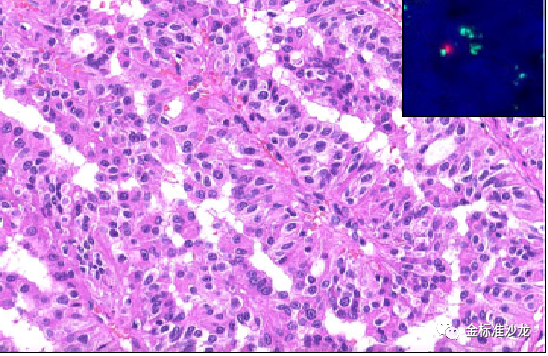

认识到pRCC在形态学存在着异质性,Delahunt和Eble首先尝试将它们分为两种类型,包括WHO2016分类仍然使用该系统且许多分子研究支持这一系统。1型pRCC通常与7号染色体(编码MET基因)17号染色体获得以及MET的体细胞激活突变相关,而2 pRCC更为异质性,且与12、16和20染色体的获得有关。1型pRCC由细乳头组成,被覆单层细胞,大多数细胞胞浆淡染,核仁不明显(图1),而2型pRCC特征包括较宽的乳头,核假复层,嗜酸性细胞质及突出核仁。然而,实际上,将pRCC一分为二可能很有挑战性,因为许多充分取材的肿瘤常常混合了类型1和类型2区域。目前的研究发现表明2pRCC可能代表几个异质性肿瘤实体,而1型pRCC基因更同质。2型pRCC核特征使这些肿瘤具有相对高ISUP的分级,可以认为不是真正代表两种独立的癌症类型,而可能代表任何pRCC从低级别到高级别的进展。重要的是, 当调整分期及其他预后因素后,1型及2pRCC并不影响患者的预后。

图1 经典的1型pRCC由纤细的乳头或管状乳头状结构组成,细胞具有淡染至嗜酸的胞浆